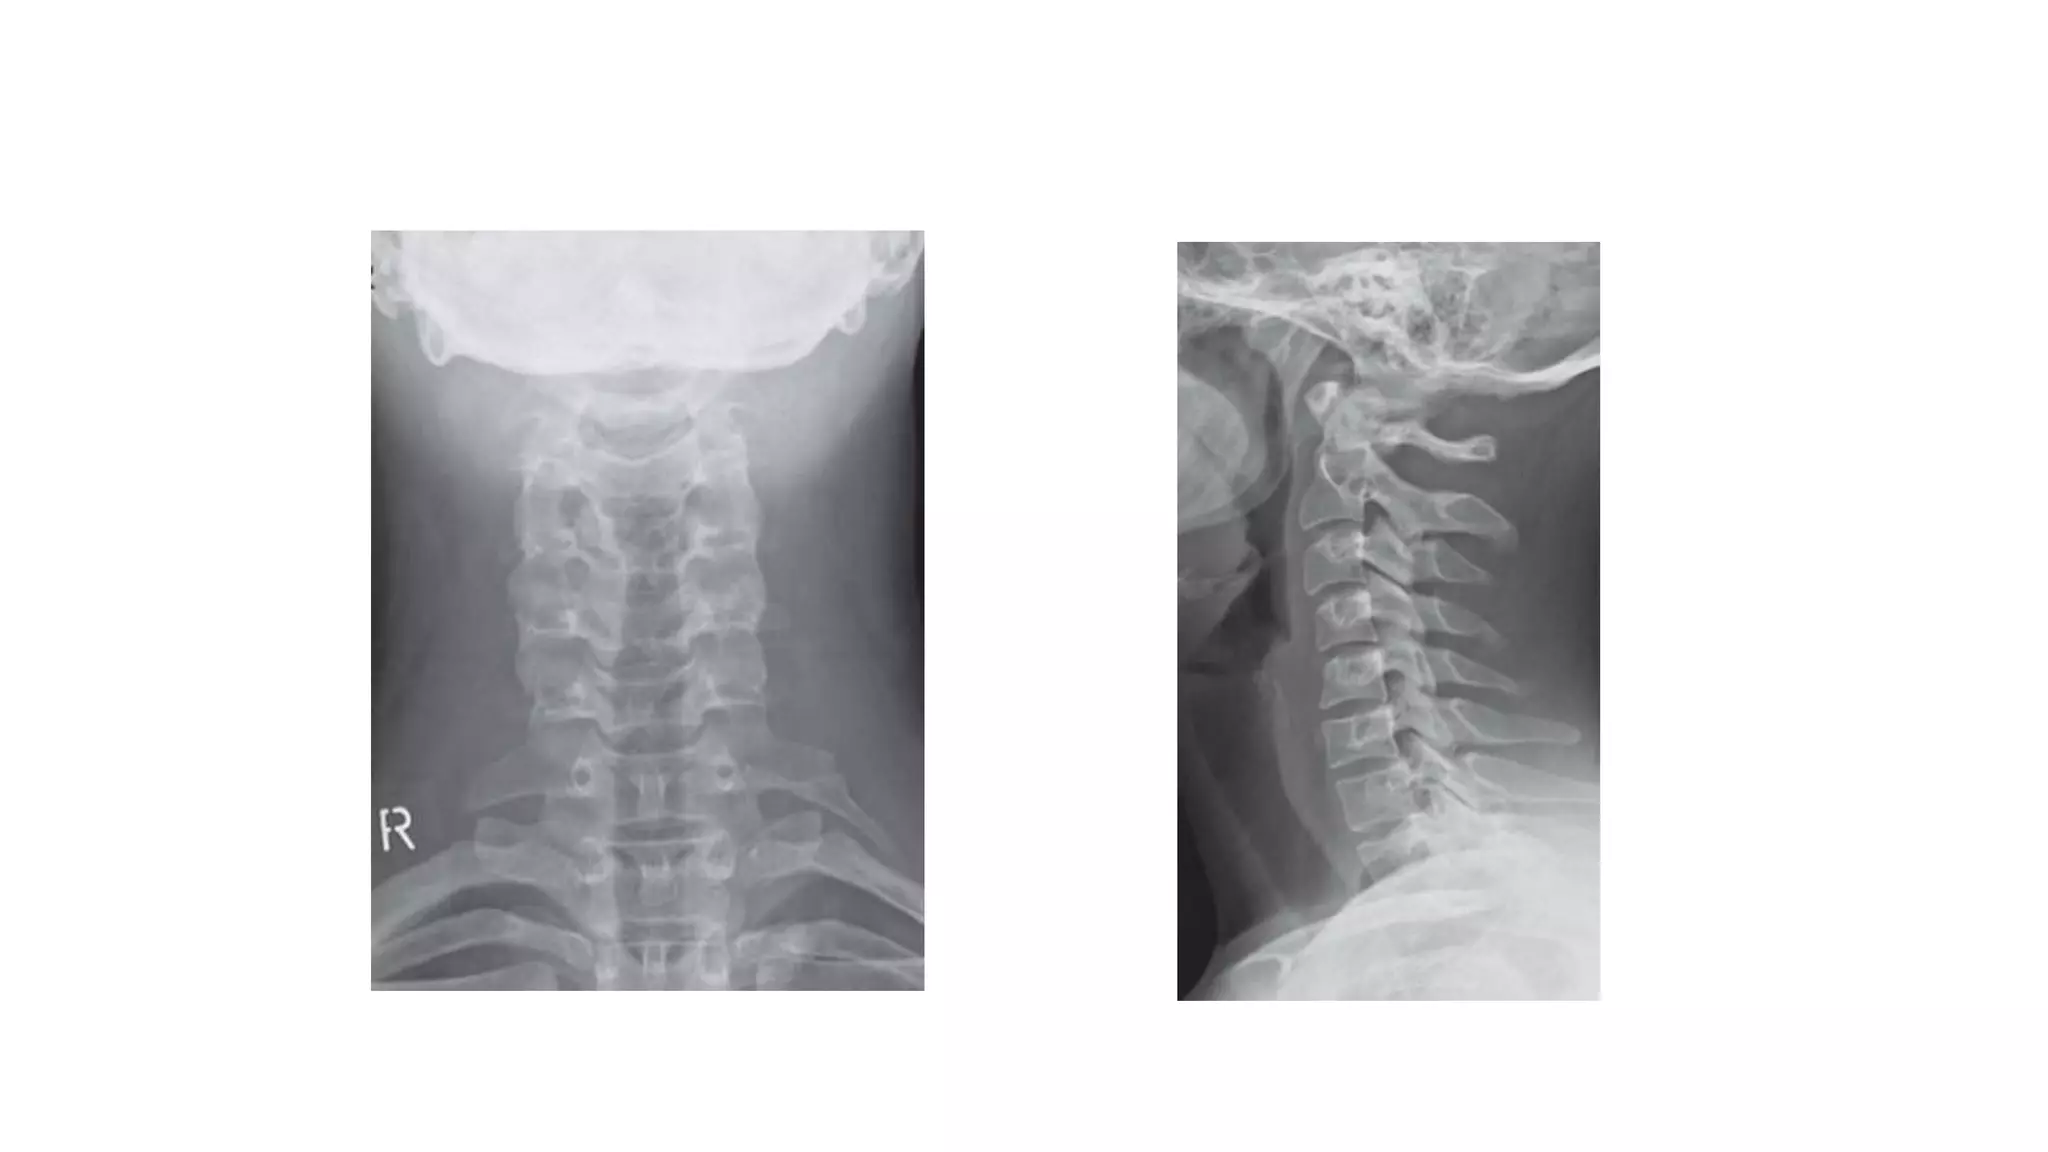

Normal plain radiography of the cervical spine

ANTERIOR POSTERIOR

VIEW

LATERAL VIEW

• 44.

Normal plain radiographyof the cervical spine ANTERIOR POSTERIOR VIEW LATERAL VIEW